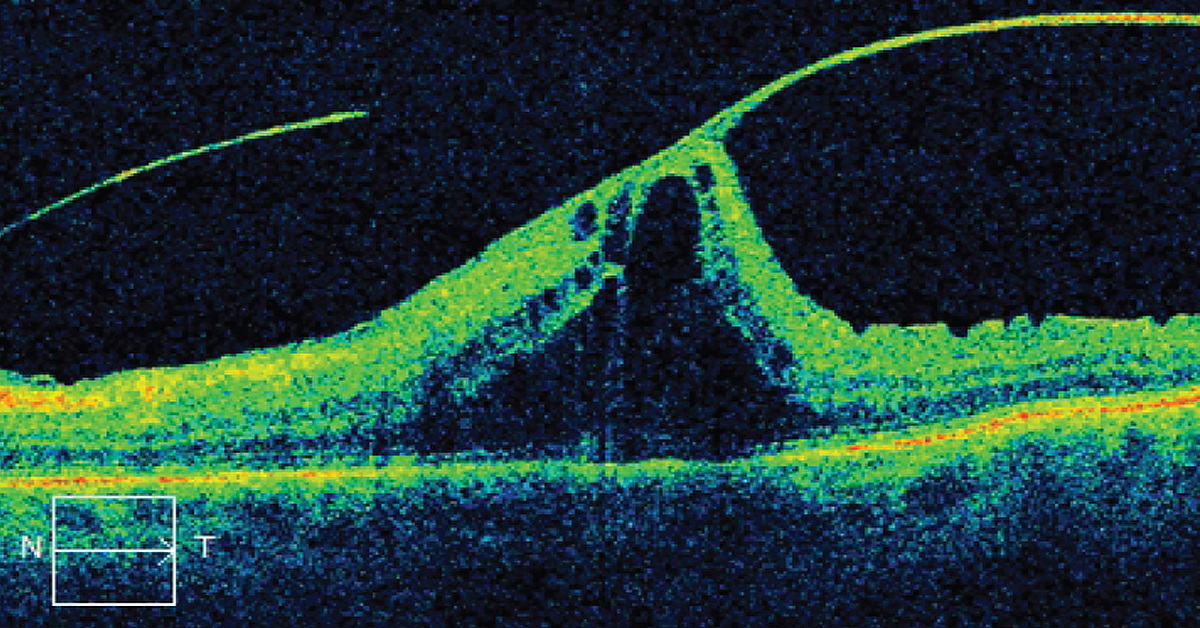

Lattice Degeneration is a thinning of the Retina that happens over time. Although 10% of the population has Lattice Degeneration, most will not have any symptoms or loss of vision as a result. Rarely, Lattice Degeneration may lead to Retinal Detachment. While doctors aren’t certain about what causes Lattice Degeneration, it’s most common in people with myopia, or nearsightedness, and in people with diseases like Stickler or Marfan syndrome. Although it is not genetically passed down from parents, those with a family history are more likely to also contract it. Lattice Degeneration doesn’t typically have symptoms, but because the Retina is thinner it is more subject to holes, tears, and breaking, which can in turn lead to Retinal Detachment, which can cause blindness if not treated immediately. Learn more about Lattice Degeneration at https://bit.ly/3gE9BM6